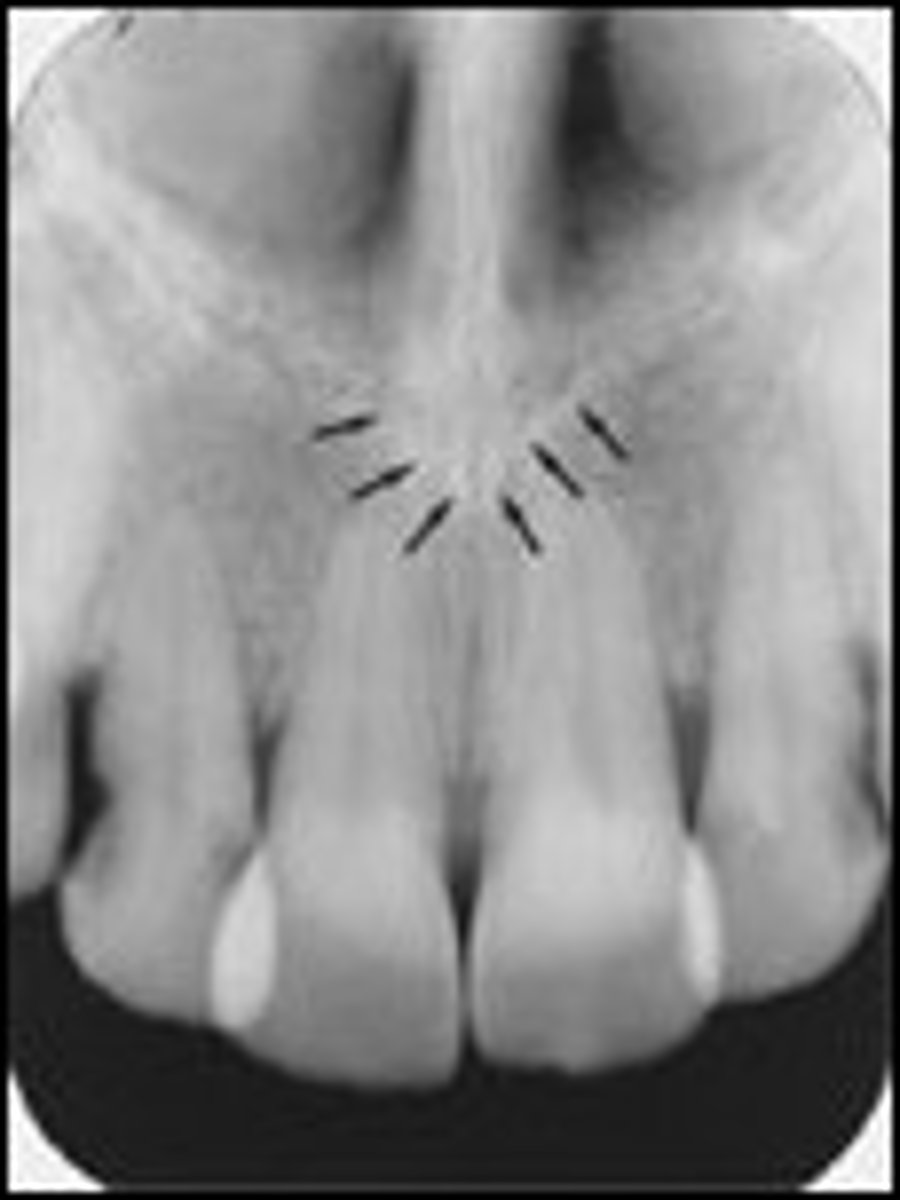

59

New cards

Genial tubercles (mental spine)

What is creating the radiopaque objects indicated by the arrows?

<p>What is creating the radiopaque objects indicated by the arrows?</p>

67

Nasopalatine duct

What is the wide, vertical structure indicated by the arrows?

<p>What is the wide, vertical structure indicated by the arrows?</p>